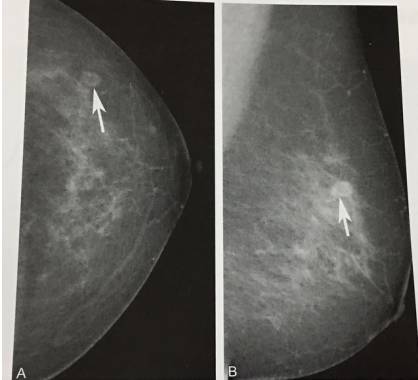

8、乳内淋巴结

患者,女,74岁。左乳外上象限环状结节影,边缘光滑(箭),手术病理证实为左乳外上象限乳内淋巴结。